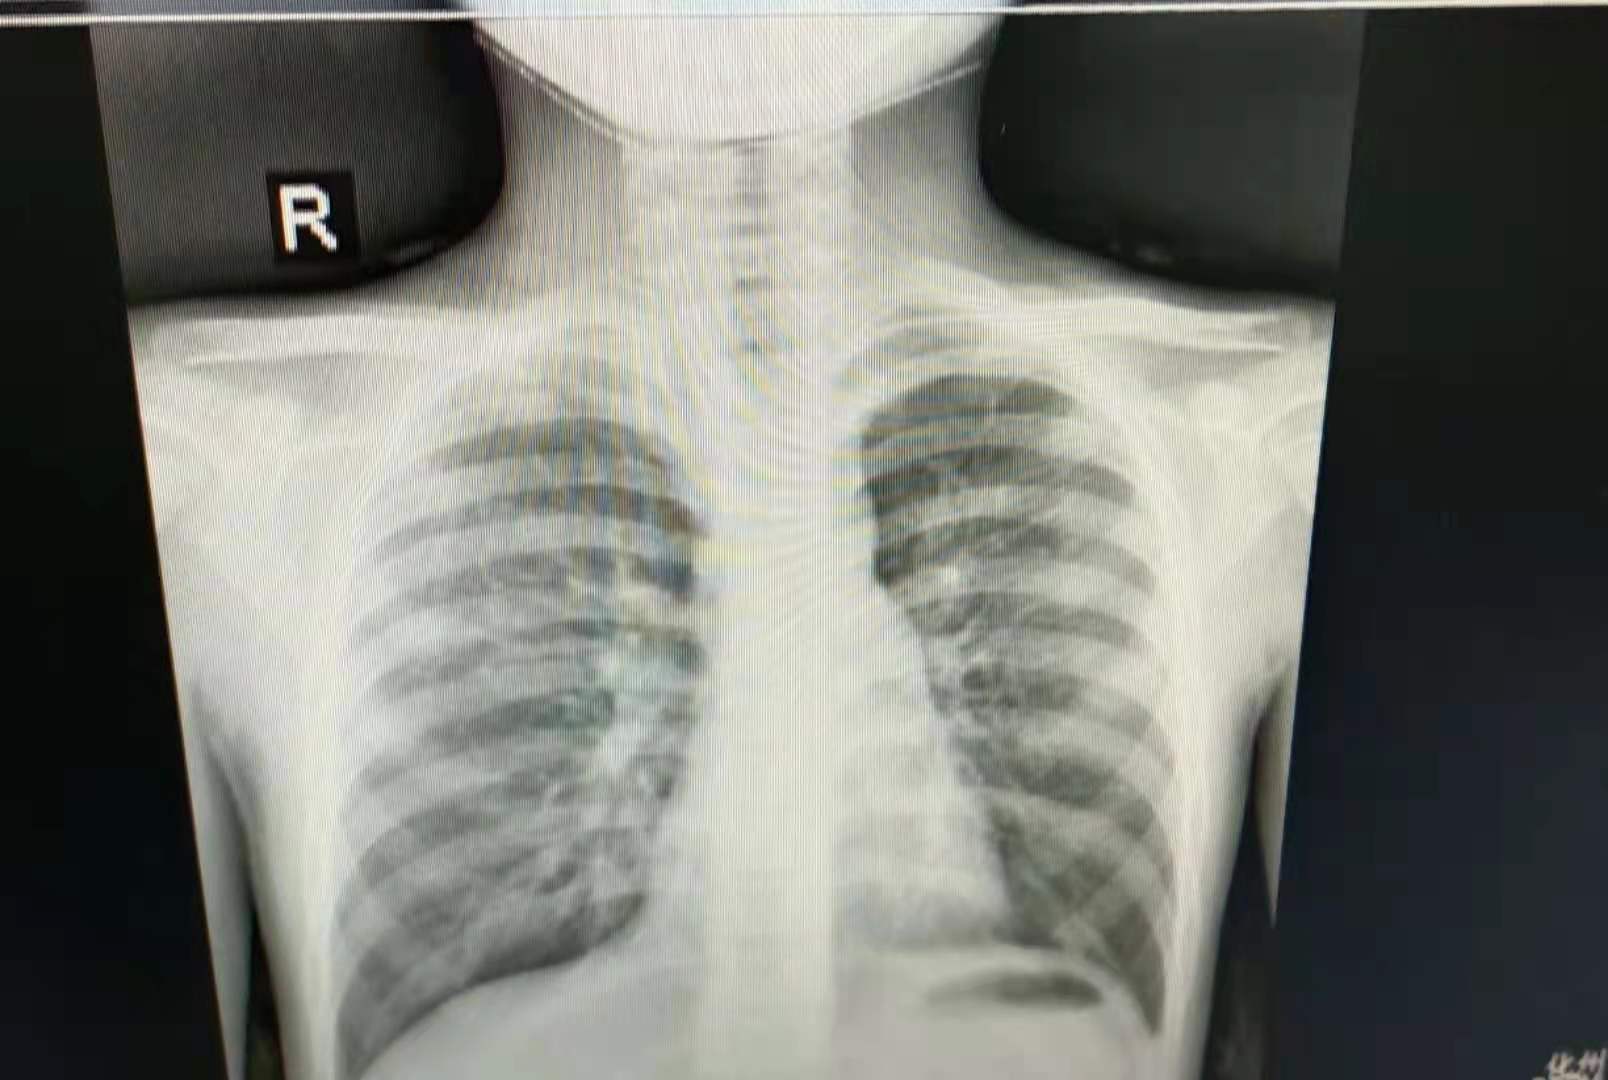

入院后完善各项相关检查,查新冠核酸检查阴性 。C反应蛋白、血清肌钙蛋白Ⅰ测定、免疫五项、风湿痛风组合、肝功能①、肺炎支原体IgM抗体检测、降钙素原、心肌酶谱六项、血气分析正常。血常规五分类:白细胞9.83X10^9/L;中性粒细胞百分比68.5%。胸片提示支气管肺炎。患者气喘,咳嗽,程度一般,为阵发性连声咳,间断性,伴咳痰,为黄白色痰,间有鼻塞、流涕,无发热,无犬吠样咳及声嘶,无呕吐、腹泻,精神可,睡眠可,饮食一般,大小便无异常。双肺呼吸音粗,双侧肺可闻及中至大量哮鸣音,心率92次/分,律齐。腹平软,肠鸣音未见异常,4次/分。

跟患儿家属谈话,患儿有咳嗽、咳痰、气喘症状,急性病程;查体发现双肺闻及固定干湿性啰音胸片提示支气管肺炎,目前诊断:支气管肺炎明确。治疗上予甲强龙、多索茶碱平喘,氯雷他定抗过敏,予布地奈德、特布他林雾化吸入等对症支持治疗。

从该病例我们知道支气管肺炎的诊断比较简单,一般有咳嗽、咳痰,呼吸短促的症状,肺部听到干湿性啰音,X线有支气管肺炎的改变时可诊断为支气管肺炎。这个患儿主要是气喘明显,有过敏体质,感染后容易出现气喘症状,治疗可予布地奈德+特布他林雾化,及予甲强龙、多索茶碱平喘治疗。该病一般需要1-2周的治疗才能康复,家长一定需要有耐心。这个孩子预后良好。